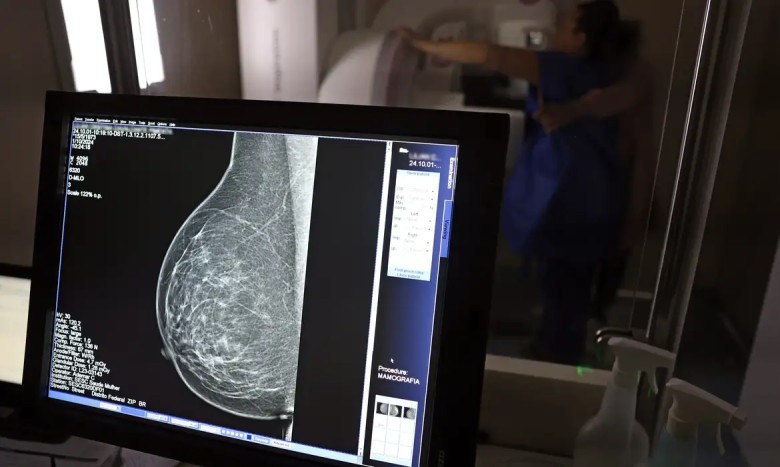

Segundo o CBR, os dados reforçam a necessidade de ampliar o rastreamento da doença por meio da mamografia também para mulheres com menos de 50 anos e acima dos 70 anos. Atualmente, a recomendação do Sistema Único de Saúde (SUS) contempla apenas mulheres entre 50 e 69 anos.

Entre janeiro de 2018 e dezembro de 2023, o país registrou 319.378 diagnósticos de câncer de mama. Do total, 157.439 ocorreram na faixa etária atualmente recomendada para rastreamento (50 a 69 anos). Já entre mulheres de 40 a 49 anos, foram contabilizados 71.204 casos. Outras 19.576 mulheres, com idade entre 35 e 39 anos, também receberam o diagnóstico, totalizando 33% dos casos fora do público prioritário.

Na população acima dos 70 anos, foram identificados 53.240 diagnósticos no período.

O levantamento mostra ainda um aumento de 59% no total de diagnósticos da doença em seis anos. Em 2018, foram registrados 40.953 casos; em 2023, o número subiu para 65.283.